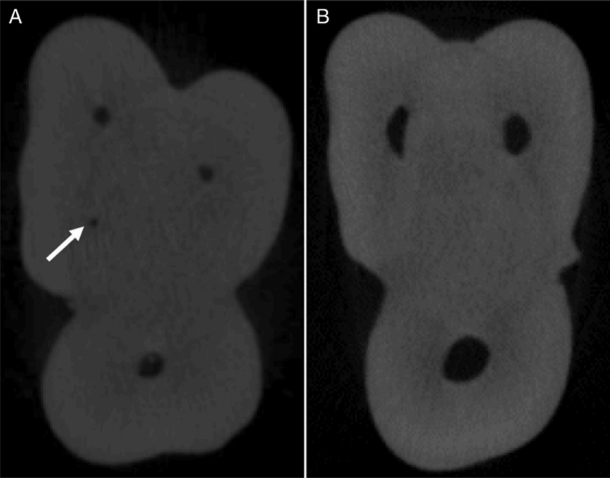

РИСУНОК 1 – Аксиальные срезы зуба, полученные методом микро-компьютерной томографии: (A) — с наличием канала MB2 (указан стрелкой) и (B) — без канала MB2.

Срезы были систематизированы (см. рис. 1) с использованием программного обеспечения NRecon (Bruker) и проанализированы двумя опытными исследователями по соглашению, с помощью программы DataViewer (Bruker).